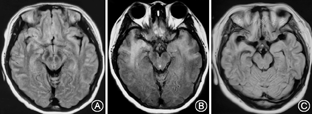

病毒性脑炎期头MRI异常信号范围累及颞叶、额叶、岛叶、扣带回,AE期病变范围较前扩大者8例,较前无明显变化者1例,较前缩小者1例(图1)。